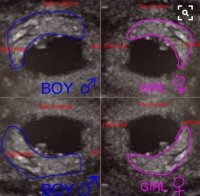

Det hvite er vel morkaken, så hvis UL er tatt innvendig, tilsier vel Ramzi-teorien at det blir jente?Vis vedlegget 303746 Hva sier dere om denne? Innvendig UL.

Det er det jeg synes er litt vanskelig å si... For jeg har disse to bildene som begge er tatt innvendig på samme ULDet hvite er vel morkaken, så hvis UL er tatt innvendig, tilsier vel Ramzi-teorien at det blir jente?

Det skjønner jeg godt, utrolig spennende å få vite kjønnet! Syns det ser ut som om morkaken er til venstre på begge bildene, altså jenteDet er det jeg synes er litt vanskelig å si... For jeg har disse to bildene som begge er tatt innvendig på samme ULJeg har en magefølelse på gutt, men nesten alle andre som sier noe om magefølelsen mener jeg får jente (inkludert mannen min og mamma)

Jeg tolker den som guttDet er det jeg synes er litt vanskelig å si... For jeg har disse to bildene som begge er tatt innvendig på samme ULJeg har en magefølelse på gutt, men nesten alle andre som sier noe om magefølelsen mener jeg får jente (inkludert mannen min og mamma)

Ser ut som en liten gutt!Jeg blir ikke klok på hvordan man skal tolke metoden.

Synes det ser ut til å være jenteDet er det jeg synes er litt vanskelig å si... For jeg har disse to bildene som begge er tatt innvendig på samme ULJeg har en magefølelse på gutt, men nesten alle andre som sier noe om magefølelsen mener jeg får jente (inkludert mannen min og mamma)

Haha, nå ble jeg bare mer forvirra siden ei over her sa guttJente.

Ved innvendig tul

Venstre side = jente, høyre side=gutt

. Men ved innvendig ul må man da holde bildene på magen, for å få rett side? Jaja...godt kjønn ikke har så mye å si for min del

Skjønner at det er forvirrende! Det er litt forvirrende hele metoden. Det er din venstre side som er jente og din høyreside som er gutt. Legg bildet på magen din med bildesiden ut så ser du hvilken side babyen ligger på I magen din. Dette gjelder bare innvendig UL derimotHaha, nå ble jeg bare mer forvirra siden ei over her sa gutt. Men ved innvendig ul må man da holde bildene på magen, for å få rett side? Jaja...godt kjønn ikke har så mye å si for min del

Er så enkelt som at ved innvendig er jente=venstre, gutt=høyre. Og da ved evt utvendig så er det motsatt, jente=høyre og gutt=venstre

Dette bildet er fra utvendig ultralyd

Som da gjør at det er motsatt ved innvendig

Den er helt lik min utvendige, som er ei jente på 2 år nå. Så jaja da går det kanskje ut ifra livmora di, men det gjør også teorien så og si like brukbar som kinesisk fødselskart, 50/50Dette er en innvendig ultralyd....for som du leser så står det top of uterus som vil si at Ramzi fullt og holdent går ut ifra DIN livmor. Uansett hvordan du tolker bildene. Du må alltid bruke livmora Di og gå etter den. Bildene er brukt som et hjelpemiddel for deg til å forstå hvor babyen ligger i livmora Di

Men hvilken uke ble dine utvendige bilder tatt? Det har mye å si...Den er helt lik min utvendige, som er ei jente på 2 år nå. Så jaja da går det kanskje ut ifra livmora di, men det gjør også teorien så og si like brukbar som kinesisk fødselskart, 50/50